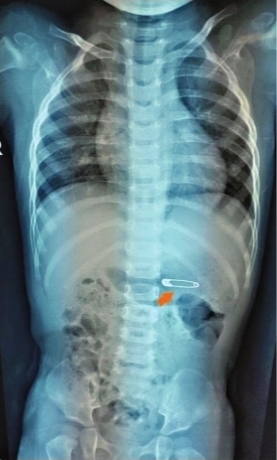

皮皮的爸妈都说没有动过别针,于是全家出动各处翻找,仍不见别针的踪影。“会不会被皮皮吞到肚子里了?”父母随即带着皮皮前往家附近的医院,通过影像检查发现那枚别针果然在皮皮的胃里,医生建议立刻转诊至湖北省妇幼保健院。

当胃镜进入皮皮胃里时,大量牛奶和食物阻挡了视野,难以寻找别针。医护们立刻启动了第二套方案,利用胃镜特制的磁铁吸出别针,因别针长约3厘米,皮皮年龄小,食管空间很小,在取出时,朱珍妮巧妙地调整角度,让别针竖着被提了出来,整个过程非常顺利。